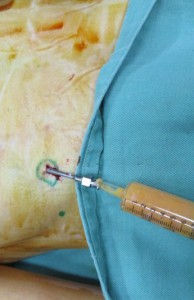

濃縮した良質な脂肪細胞をバストに注入します